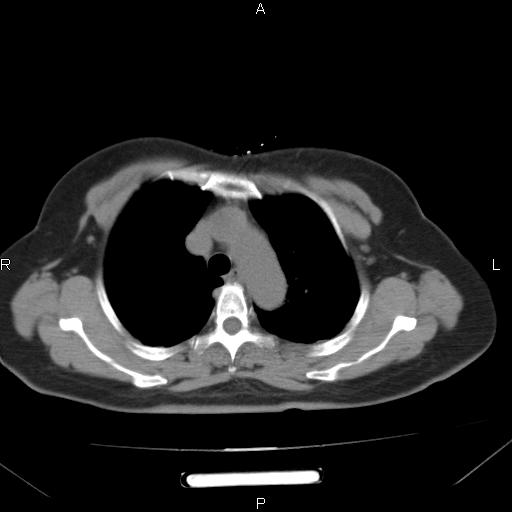

胸腺瘤

女、63Y 双眼睑下垂,早轻晚重。 胸腺瘤???

结果胸腺瘤